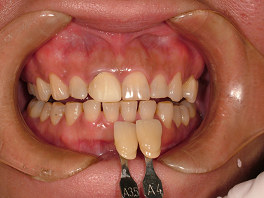

二人目の患者さんも30台の女性の方です。左の一番前の歯が黒いことを気にして来院されました。

この方は、ホワイトコートを希望されて来院されましたが、上の方のグラディアダイレクトの写真とこの後に紹介しているホワイトコートの写真を較べて、グラディアダイレクトをすることになりました。

今回は、歯並びは問題ないのですが、このことで逆に難しくなります。

詰めた分だけ厚みがでて唇に違和感が生じないかどうかです。

しかし、きわめて少ない量で、色を出すことができました。厚みもとても薄くでき、本人にもとても喜んでもらうことができました。

このケースもまったく歯を削っていません。

術前 ↓

術後

隣の歯に合わせて、あまり白くせずに自然な色にしました。